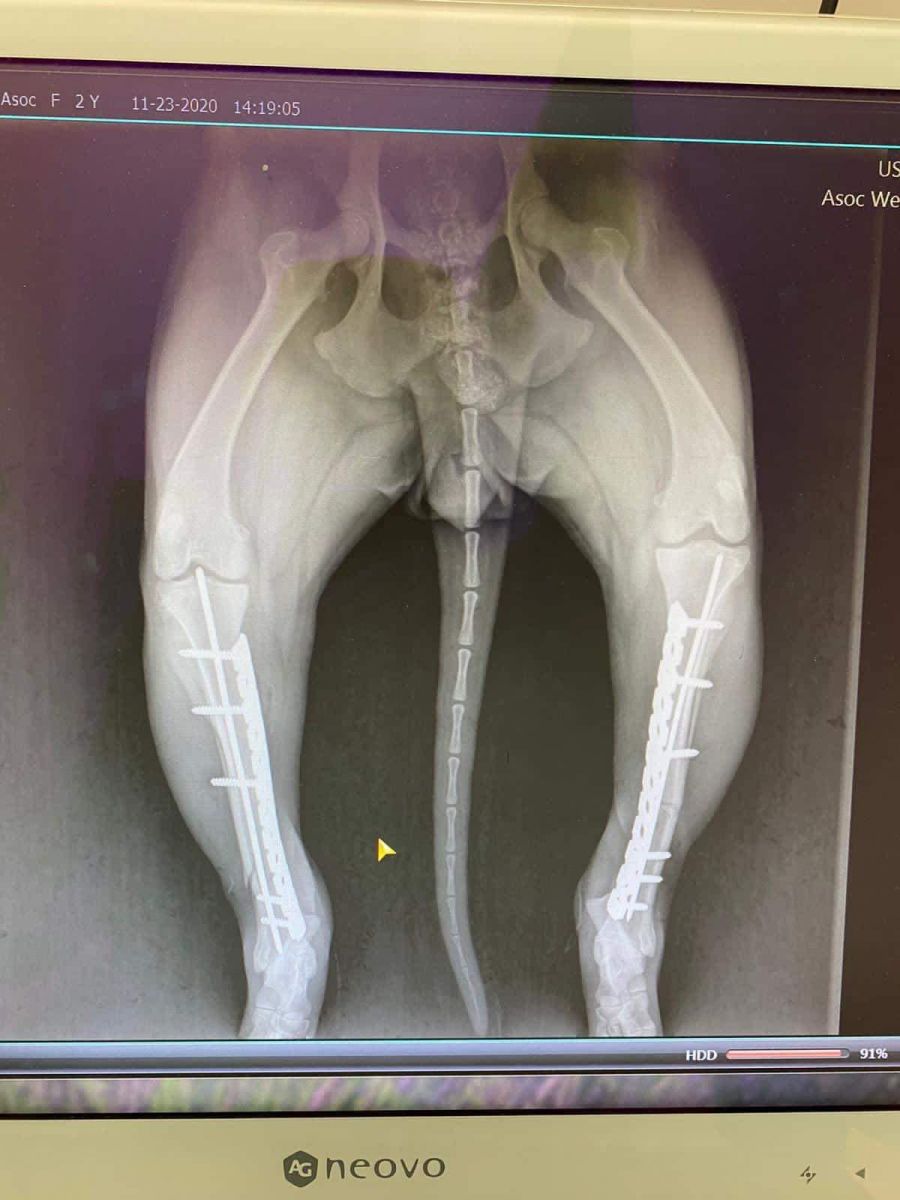

Prinsă în laț și bătută cu atâta cruzime încât i-au rupt picioarele, cățelușa a fost adusă de niște oameni miloși în cabinetul medicilor veterinari.

În urma investigațiilor și radiografiilor s-a confirmat că ambele membre posterioare prezentau fracturi duble, unul din membre cu fractura semideschisă, însă încă prezentau sensibilitate”,

Operația s-a realizat de urgență, totul a decurs bine, dar există în continuare risc de infecție, astfel că va mai rămâne internată câteva zile în clinică, recuperarea fiind una de durata.

”Tot ce putem face este să sperăm că totul va fi bine. Mulțumim prietenei și colegei noastre Lidia Zahiu, care ne-a ajutat extrem de mult cu chestiile organizatorice acolo la Cluj. Mulțumim tuturor pentru mesajele frumoase și încurajatoare, mulțumim de asemenea și pentru ajutorul acordat. Pentru cine dorește sa ajute la achitarea facturilor medicale și a transportului o poate face printr-o mică donație în contul Asociației We Care About Strays RO69RZBR0000060018778836. Vă mulțumim”,